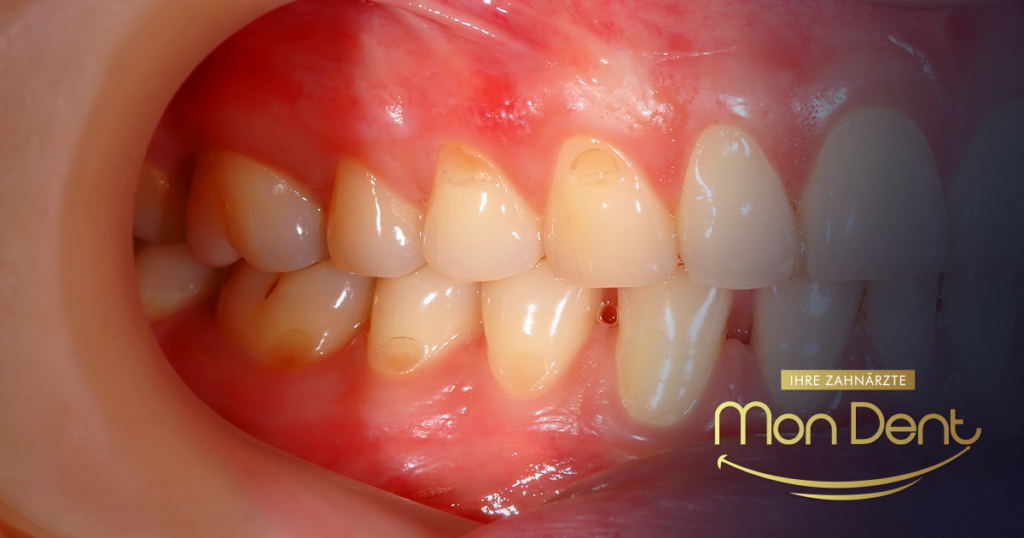

Sintomi della parodontite: come riconoscerla precocemente

Riconoscere precocemente i sintomi può salvare i denti. Ecco i segnali più comuni:

- Sanguinamento delle gengive durante lo spazzolamento o l'uso del filo interdentale: questo è il primo segnale d'allarme.

- Arrossamento, gonfiore o dolorabilità delle gengive.

- Alito cattivo (alitosi) che non passa.

- Gengive ritirate, che fanno apparire i denti più lunghi.

- Formazione di tasche tra le gengive e i denti.

- Denti che tremano o si muovono.

- Dolore durante la masticazione o perdita dei denti negli stadi avanzati.